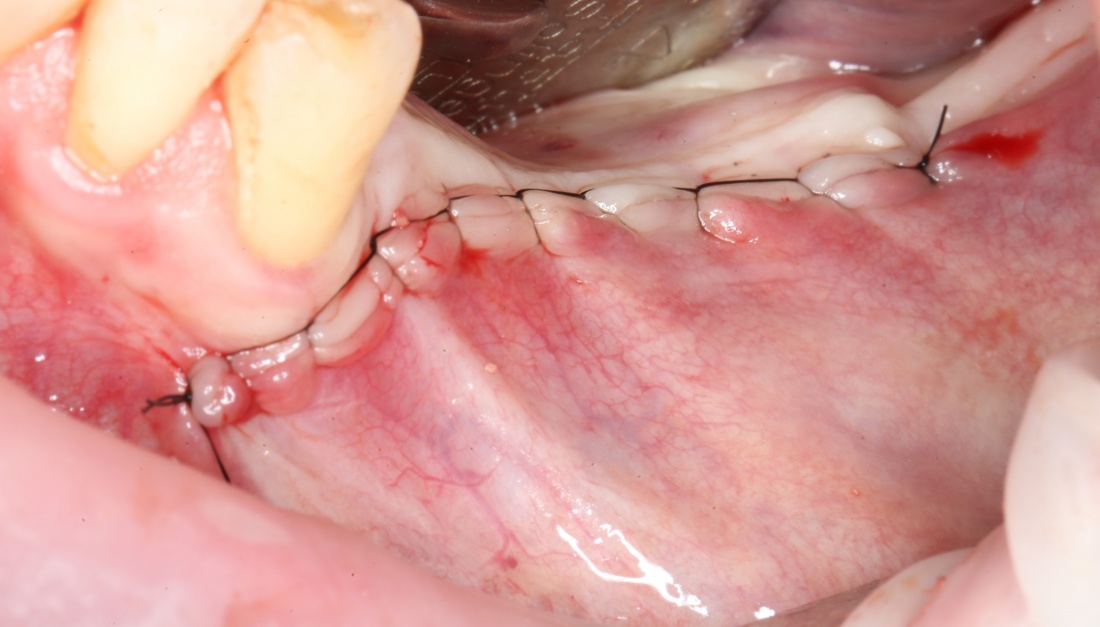

Если на этапе разреза и формирования раны всё сделано правильно, то наложение швов не вызывает особых трудностей. Периостотомия или послабляющие разрезы на периосте не требуются (ни практически никогда не требуются). А сами швы получаются аккуратными и герметичными:

Обрати внимание, что все шовные лигатуры находятся в пределах кератинизированной десны. Это позволяет избежать деформации тканей и лишних рубцов. В наиболее уязвимых местах (около зубов) шовные лигатуры лучше продублировать.

Если бы мне пришлось делать это сейчас, то я бы использовал непрерывный «матрацный» шов. Он удобнее, быстрее в наложении и комфортнее для пациента. Минус — если распускается, то распускается весь. К тому же, его очень неудобно снимать.

Несмотря на то, что уже тогда мы широко использовали непрерывные швы в подобных случаях, здесь я, во-первых, зассал (может распуститься), во-вторых, снятие швов предполагалось в поликлинике по месту жительства пациентки, и мне не хотелось, чтобы там при снятии швов начудили. Как выяснится позже — зря беспокоился.

Неизменно одно — в таких операциях мы использовали и до сих пор используем нерезорбируемые монофиламентные шовные материалы, поскольку они наиболее гигиеничные. Чтобы острые концы нитей не беспокоили пациента, их можно оплавить нагретой гладилкой или гуттаперчевым плаггером.